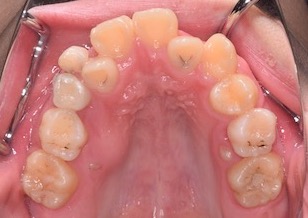

BeforeⅡは、治療前の上顎歯列です。

上下顎歯列に叢生(ガタガタの歯並び)を認めます。